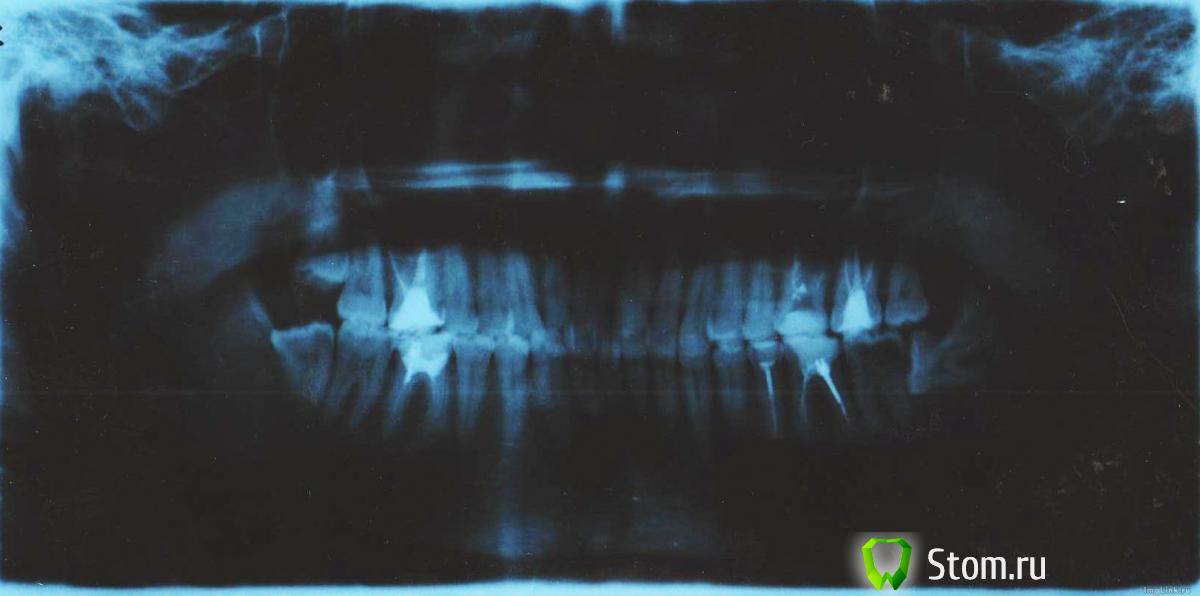

aesnn Опубликовано 29 января, 2012 Поделиться Опубликовано 29 января, 2012 (изменено) История очень длинная, речь пойдет о левой стороне головы =). Итак прошлой зимой было очень холодно и после пребывания на улице свыше 10 минут я начал замечать неприятные ощущения в районе 6-7 зубов верхней челюсти слева. Т.е. при промерзании губы либо вдыхании холодного воздуха. На тот момент 6 зуб был теоретически мертвым, 7 зуб с небольшой пломбой на поверхности. Итак начались походы по консультациям (платным) в разнообразные клиники. Боль воспроизвести не удавалось ни воздухом ни водичкой ни постукиванием. Внешне все хорошо - и десна и снимки. Поскольку никто не мог внятно установить источник боли я решил убить 7 зуб, его пролечили но это не помогло... Далее я перелечил зуб 6 (на снимке он не перелечен). До этого перелечивания я ходил на кафедру на платную консультацию (откуда собственно и снимок) где тетенька профессор (или кто - не разбираюсь в званиях) открыла студентам стоматологическую тайну при мне. Сказала что если болит - она сначала говорит - снять протезы, если продолжает болеть - удалить зубы. Короче на этой консультации тоже ничего не обнаружилось - десны красивые, карманов нет, нервы пощупали лицевые и т.д. Рекомендовали удалить зуб мудрости для начала нижний. Далее я перелечил 6 зуб. На какоето время вроде прошло, но теперь опять боли, а именно:Боль возникает при приеме пищи (кислой, сладкой, холодной, горячей). Причем локализовать ее невозможно и повторить тоже. Сначала резкий всплеск в районе 5-6-7 десны, далее по нарастающей жжение десны монотонное целиком. Чистка нитью, щеткой, пастой не помогают. Помогает найз причем иногда 1 таблетка, иногда и 3 не спасают. Летом болело сильнее - с захватом и пульсацией в затылок. Когда перелечивал 6 зуб верхний стоматолог не смогла пройти один канал, сказала что там что-то твердое как стекло, видимо это результат биплатного лечения склеротирующей пастой ранее. Стоматологу не доверять оснований нет - квалификация и современные инструменты в наличии, остальные зубы пролеченные в норме. Причем у меня была проблема в 6 зубе справа - там был непролеченный канал, который потом успешно пролечили и ноющие боли и реагирования на погоду прекратились. Т.е. я понимаю как болит непролеченный канал - вот в ситуации слева боль абсолютно не такая, болит скорее десна. Вопросы:1) Может ли хроническое воспаление в кармане кривого зуба мудрости выползать наружу по кратчайшему расстоянию в верхнюю челюсть и вызывать вялотекущее воспаление десны в результате которого она так болезненно реагирует на пищу (температуру?) 2) Удалять зуб мудрости и ждать что будет дальше? 3) При такой конфигурации зуба мудрости насколько болезненным будет заживление, нетли там каких важных нервов чтоб лицо не перекосило? 4) Или может как-то установить источник боли можно? 5) Что делать и в какой последовательности? 6) А может ли кривой нижний зуб влиять на верхнюю десну както (что там с нервными конфигурациями) ? Например установлена взаимосвязь зубов с внутренними органами, может такая есть и взаимная, т.е. из-за зуба мудрости болит верхний (он там корнями непонятно куда упирается, может меня вообще всего перекосит?) Я нахожусь в Нижнем Новгороде. Парадонтолога в городе я так и не нашел провериться на предмет болезни десен. http://saveimg.ru/pictures/29-01-12/29ddc8aebdd2ae82ae45ec6c2eaf20d9.jpghttp://saveimg.ru/pictures/29-01-12/655d1409e142be42d63e365fb49eed76.jpghttp://saveimg.ru/pictures/29-01-12/bddb60301875d93e0471d8e1a0498ddf.jpghttp://saveimg.ru/pictures/29-01-12/116e22cc7eec04edd16384f5b1111a92.jpghttp://saveimg.ru/pictures/29-01-12/2513b70f452e82d77327c84eeb4eb784.jpg Изменено 29 января, 2012 пользователем aesnn Ссылка на комментарий

Stomart Опубликовано 29 января, 2012 Поделиться Опубликовано 29 января, 2012 По снимкам у вас проблема с 7-м нижним зубом слева Ссылка на комментарий

DmitrySH Опубликовано 29 января, 2012 Поделиться Опубликовано 29 января, 2012 У вас на снимке на седьмом зубе обширная кариозная полость через которую происходит инфицирование нерва седьмого зуба. + с восьмым зубом нужно расстаться Ссылка на комментарий

ger_berra Опубликовано 30 января, 2012 Поделиться Опубликовано 30 января, 2012 Причинный зуб у Вас нижний левый 7-й.Пульпитные боли от нижних зубов могут иррадиировать (распространяться) на зубы верхней челюсти,в висок,в голову,в соседние зубы.В 6-ке рядом с ним надо перелечить каналы.Там воспаление на верхушке корня,тоже может периодически обостряться.Зуб мудрости здесь же удалять без промедлений.Из-за него испортился 7-й. Ссылка на комментарий

shishok Опубликовано 2 февраля, 2012 Поделиться Опубликовано 2 февраля, 2012 Да,дырявое дно-удалять без вариантов А судя по снимку кариозная полость там давно,причём все доктора,отвечавшие Вам на форуме,нашли её без проблем. Ссылка на комментарий